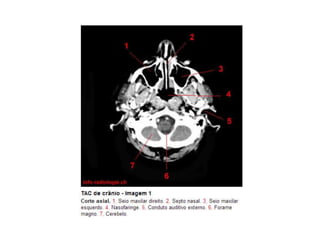

Anatomia E Protocolo Tomografia Computadorizada de Crânio PPT

Anatomia Seccional do Crâneo em Tomografia Computadorizada PPT